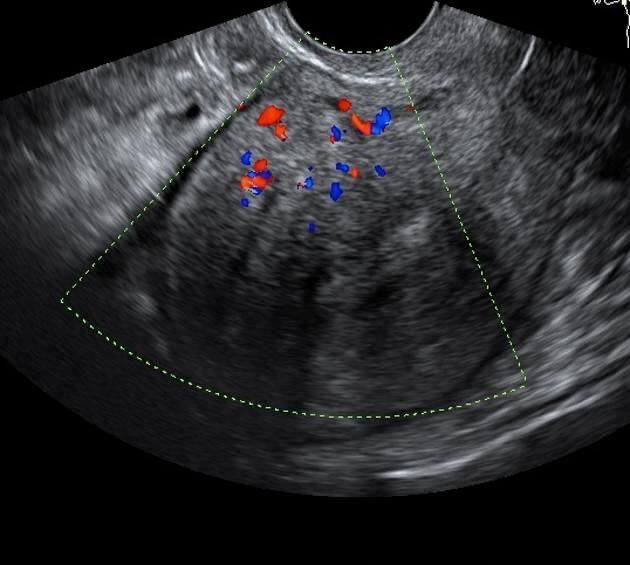

Очень часто встречается такая клиническая ситуация. Пациентка приходит с заключением УЗИ малого таза к гинекологу, в заключении написано — аденомиоз (эндометриоз матки), и только на основании написанного в УЗИ врач гинеколог назначает пациентке например КОКИ (гормональные контрацептивы), зачастую с такой формулировкой — на всякий случай, чтобы не стало хуже, а пациентку при этом ничего не беспокоит.

По УЗИ малого таза выявлен эндометриоз матки, а при этом у пациентки нет никаких симптомов, нет ни обильных и болезненных менструаций, нет длительных кровянистых мажущих выделений до и после менструации. В данном случае не требуется назначение препаратов, только наблюдение 1 раз в год.

2. Если пациентка в настоящее время планирует беременность, а у нее выявлены эндометриоидные кисты до 3-3,5 см, в этом случае не требуется ни оперативное лечение, ни лечение гормонами. Возможно планирование спонтанной беременности.

3. Если эндометриоидные кисты более 4 см, то бессмысленно пытаться их полечить гормонами. В этой ситуации необходимо только оперативное лечение. Но если у пациентки есть в настоящее время или в будущем репродуктивные планы, обязательно оценка фолликулярного резерва и консультация репродуктолога, поскольку в отдельных случаях перед операцией у таких пациенток может потребоваться проведение банкинга яйцеклеток.